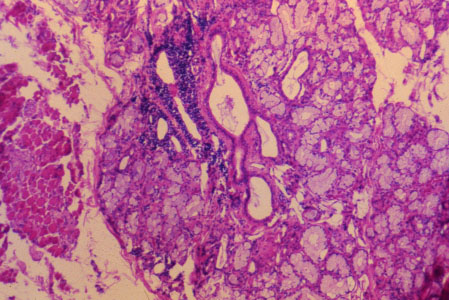

K-slide 27: Still higher magnification of slide 25

Buccal salivary glands are classified as seromucous, as shown here.